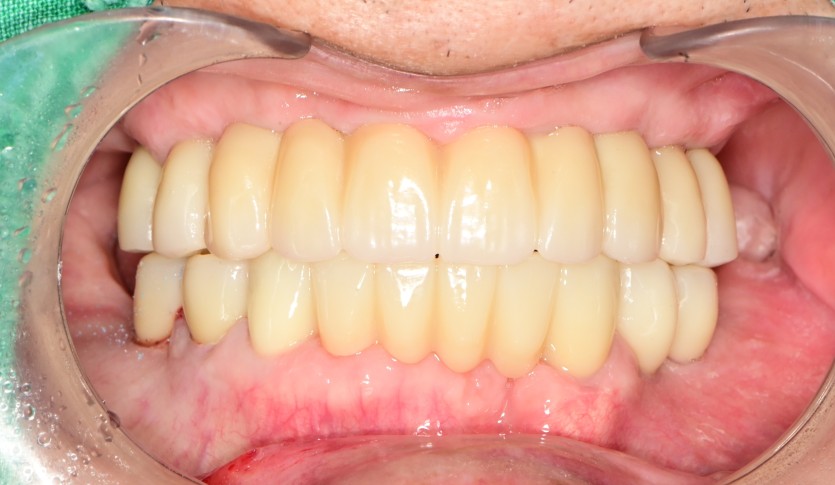

만 73세 전체 임플란트 중례

상, 하악 전체 임플란트 증례입니다.

14개의 임플란트로 완성하였습니다.